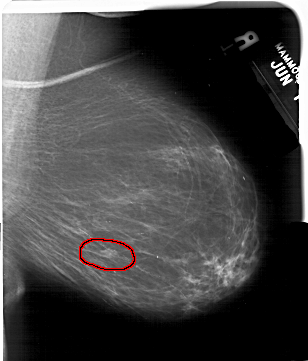

A_1532_1.LEFT_MLO

LEFT_MLO LINES 5911 PIXELS_PER_LINE 4501 BITS_PER_PIXEL 12 RESOLUTION 43.5 NON_OVERLAY

FILE: A_1532_1.RIGHT_MLO.OVERLAY

TOTAL_ABNORMALITIES 1

ABNORMALITY 1

LESION_TYPE MASS SHAPE OVAL MARGINS ILL_DEFINED

ASSESSMENT 4

SUBTLETY 3

PATHOLOGY MALIGNANT

TOTAL_OUTLINES 1

BOUNDARY